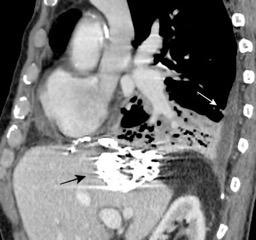

T. mixto de células germinales del testículo

izquierdo Metástasis pulmonares. (flechas verdes). Ganglios paratraqueales. (flechas amarillas). Ganglios retroperitoneales (flechas negras)

Nódulos pulmonares múltiples. (flechas verdes). Masas paratraqueales. (flechas amarillas). Dudoso ensanchamiento retrocrural (flechas negras). sigue….

Ttawfik A et al. Trans-diaphragmatic Pathologies: Anatomical Background and Spread of Disease on cross-sectional Imaging. Current Problems in Diagnostic Radiology. 2021.

Tawfik A et al. Trans-diaphragmatic Pathologies: Anatomical Background and Spread of Disease on cross-sectional Imaging. Current Problems in Diagnostic Radiology. 2021.